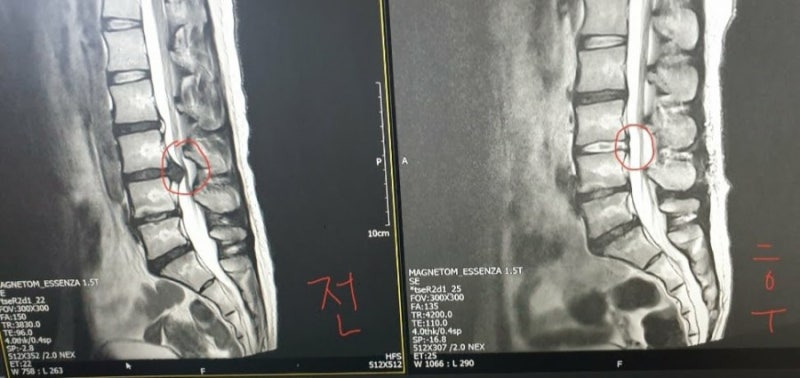

또 다른 환자는 수술 후 MRI를 통해 허리 상태가 개선된 것을 확인했어요. 수술 전과 후의 MRI를 비교해보면, 문제가 있었던 디스크가 제거된 것을 볼 수 있어요.